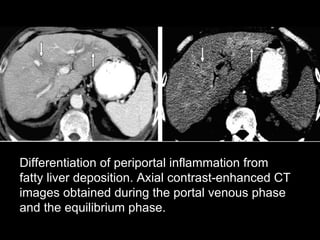

Differentiation of periportal inflammation from fatty liver deposition. Axial contrast-enhanced CT images obtained during the portal venous phase and the equilibrium phase.

Differentiation of periportalinflammation from fatty liver deposition. Axial contrast-enhanced CT images obtained during the portal venous phase and the equilibrium phase.